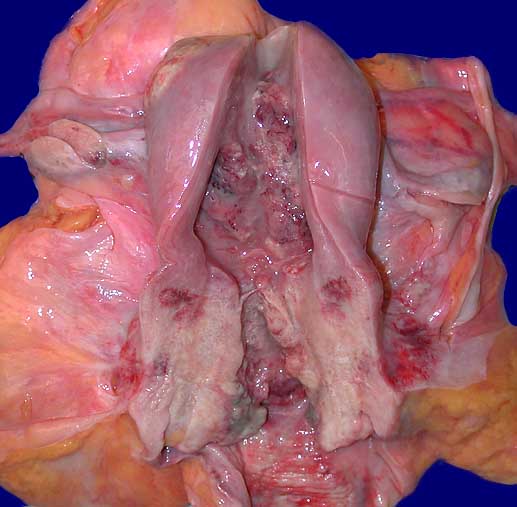

Karzinome unterscheiden sich von einem Carcinoma in situ durch zungenförmige Tumorausläufer, welche die Basalmembran durchbrochen haben oder die Anwesenheit von kleinen Zellnestern ohne Basalmembran in desmoplastischem Stroma. Das invasive Karzinom verursacht meist eine Stromareaktion in Form eines Ödems, einer desmoplastischen Fibrose, chronischer Entzündung oder einer granulomatösen Entzündung. Makroskopisch können die invasiven Tumoren exophytisch polypoid, papillär, oder endophytisch wachsen. Bei den invasiven Karzinomen unterscheidet man verhornende und nicht verhornende Karzinome, wobei der Verhornungsgrad keine prognostische Relevanz besitzt.

Kleine Tumoren sind oft asymptomatisch. Selten werden intermittierende, oft postkoitale vaginale Blutungen beobachtet. Fortgeschrittene Karzinome verursachen blutigen Ausfluss, Schmerzen oder Symptome im Zusammenhang mit der Infiltration von Harnblase, Rektum oder Lymphknoten. Die Karzinomdiagnose wird meist bioptisch gesichert.

• Portio mit vorderer Muttermundslippe, Anteile der hinteren Muttermundslippe und Zervikalkanal.

Makroskopie

Befund

Pathologischer Befund